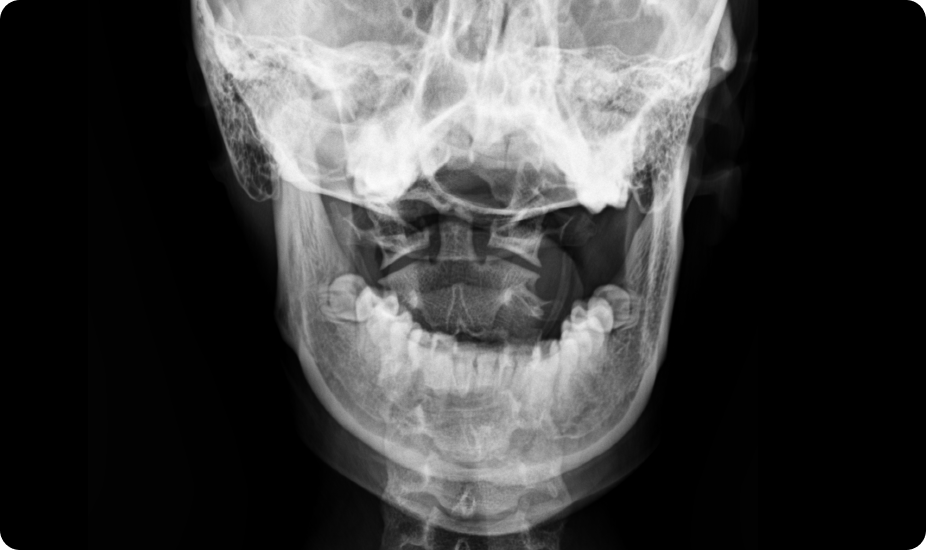

턱관절 장애를 동반한 성장부진

턱관절의 비대칭이나 불균형은 경추 1, 2번의 틀어짐과 두개골의 비대칭을 유발하여 뇌하수체에서 분비되는 성장 호르몬과 성호르몬에 영향을 줄 수 있습니다.

턱관절 부정교합 턱관절 및 상부경추교정 (성장호르몬 전달기능 개선)

상부경추 틀어짐

턱관절장애 교정

턱 위치를 바로잡아 접형골의 틀어짐을 교정, 뇌하수체 기능향상을 통해 성장 호르몬 분비 촉진